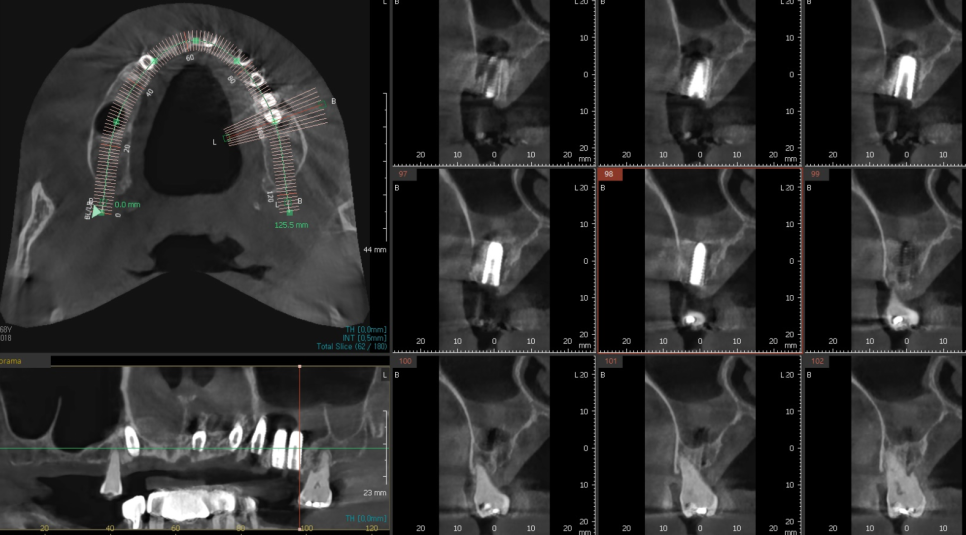

전체적인 식립이 필요한 전악 임플란트는

무엇보다 정확한 위치가 생명인데요.

저희는 내비게이션 임플란트를 통해

더 안전하고 정교하게 수술을 진행합니다.

수술 전에 컴퓨터로 환자분의

잇몸 뼈를 3D로 미리 그려봅니다.

어디에 위험한 신경이 있는지

미리 다 들여다보고

가장 안전한 길을 찾아내어

가상으로 미리 심어보는 과정을 거치죠.

정확한 위치를 미리 알고 있으니

잇몸을 넓게 열어볼 필요가 없습니다.

딱 필요한 자리에 작은 구멍만 내어

심을 수 있어 출혈이 적고,

수술 후 겪으시는 붓기나 통증도

눈에 띄게 줄어듭니다.

치아를 많이 심어야 하는 분들은

각도가 조금만 어긋나도

나중에 보철물이 불편할 수 있습니다.

디지털 가이드가 정해진 위치를 딱 잡아주니

오차 없이 튼튼하게 자리를 잡을 수 있습니다.